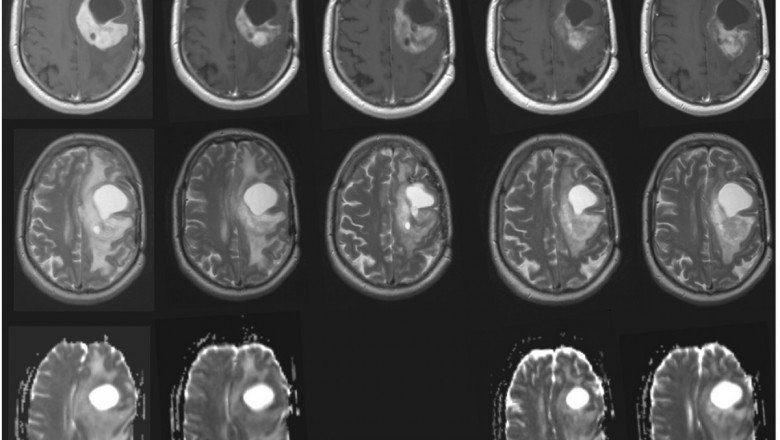

Glial cells, the brain's supporting tissue, give rise to gliomas, which are brain tumours. Glioblastoma multiforme is the most prevalent and dangerous variety of glioma (GBM). First, surgery is used to remove as much of the tumour as feasible, then radiation therapy (60 Gy in 30 fractions) and chemotherapy (concurrent and adjuvant temozolomide) are used for Recurrent Glioblastoma Multiforme Treatment (NCCN 2018). The duration of the initial course of treatment is roughly nine months. In reasonably fit individuals under the age of 70, chemotherapy has been linked to median progression-free survival of 6.5 months and median overall survival of 14.6 months. Two years after diagnosis, 25% of patients having chemoradiotherapy are likely to still be alive, compared to 10% of those receiving radiotherapy alone.